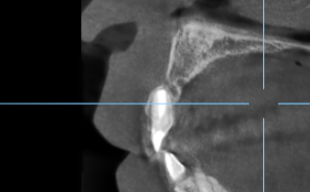

上唇の腫脹を認め、CT検査にて根尖部に嚢胞様透過像を認めた。左上の前歯が不自然に大きく噛み合わせが強くなっていたことがフレアアップの一因と考える。精密根管治療を行い、感染経路を遮断したのち歯根端切除術にて嚢胞を摘出した。

治療前